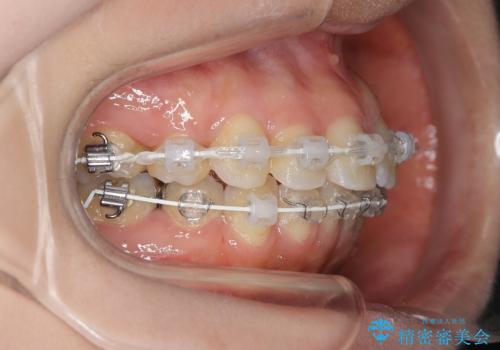

前歯のガタつきを改善 抜歯矯正後の後戻り

- 矯正装置

- 審美装置

- 抜歯矯正後の後戻りで前歯ガタつきが主訴で来院された患者様です。

後戻り矯正や非抜歯矯正はインビザラインをご案内する事が多いですが、自己管理の煩わしさから、目立たないワイヤー装置にて矯正治療を行うこととしました。

後戻りの程度としては軽度なので、治療期間としては短く終えることが出来ました。

前歯の正中線も改善され大変満足して頂きました。